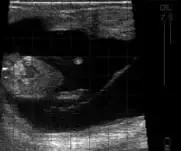

Bovine Fetus approx 71 days

Bovine Fetus – approx 71 days.